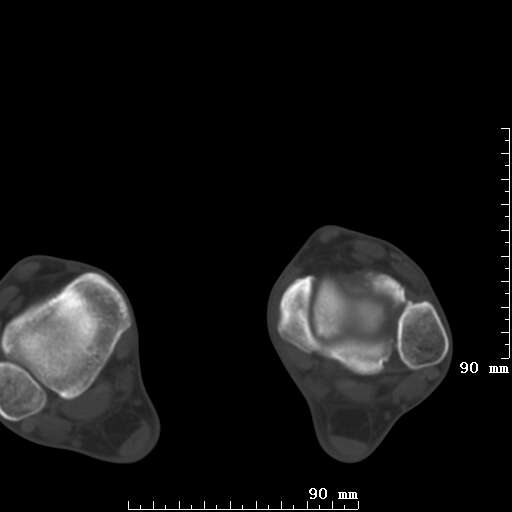

标题: CT19820:外伤一天,如何定性.男27Y [打印本页]

标题: CT19820:外伤一天,如何定性.男27Y

排除下创伤性关节炎吧,距骨有些囊变和硬化,周围韧带软组织有些机化、钙化。不是很像距骨无菌性坏死,感觉在关节面上的多,而不是距骨里面。

未见骨折及脱位像。距骨像是剥脱性软骨炎

支持!(踝关节距骨表面囊变和硬化 缺损)

距骨剥脱性软骨炎可能;踝关节创伤性关节炎?

未见明确新鲜骨折改变,距骨剥脱性软骨炎或踝关节创伤性关节炎可能。